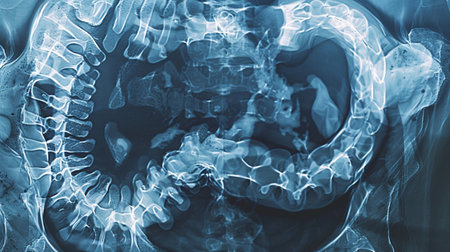

barium enema demonstrated cecum and colon for diagnosis Colorectal cancer or colon cancer.